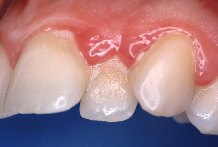

Es muy

importante saber c�mo limpiarse los dientes con la m�xima eficacia. El verdadero peligro

lo representa la invisible acumulaci�n de bacterias que crecen sobre y alrededor de los

dientes, o sea, la placa. Afortunadamente la placa bacteriana se puede ver aplicando unas

pastillas colorantes en la boca. Dichas pastillas ti�en la placa, no dejando ninguna duda

sobre su presencia y posici�n.

El dentista y la higienista dental deben establecer un programa de higiene bucal para cada individuo. Tal programa debe incluir instrucci�n sobre c�mo cepillarse de un modo apropiado para no perjudicar ni a los dientes ni a las enc�as. El uso de la seda o cinta dental es la forma m�s adecuada para eliminar la placa bacteriana de entre los dientes que es un lugar dif�cil de alcanzar. Son en estos lugares donde se forman m�s com�nmente las bolsas periodontales. Por tal motivo, y para evitar su formaci�n, merece la pena dominar la t�cnica de usar la seda dental aunque sea necesario emplear m�s tiempo en la higiene bucal.

El uso del cepillo interdental y los aparatos que irrigan agua a presi�n pueden suplementar las t�cnicas de higiene en �reas que son dif�ciles de alcanzar con otros m�todos. Aunque estos irrigadores no remueven la placa, pueden, sin embargo, remover los restos de comida que pueden favorecer la formaci�n de placa.

La higiene bucal diaria puede reducir a un m�nimo la formaci�n de la placa bacteriana y c�lculo. Por medio de la higiene bucal no se puede eliminar el c�lculo ya formado y adherido al diente que aparece en los bordes o por debajo de la enc�a. S�lo un dentista o una higienista pueden remover el c�lculo. Dicha t�cnica se llama raspaje y se realiza con instrumentos especiales.